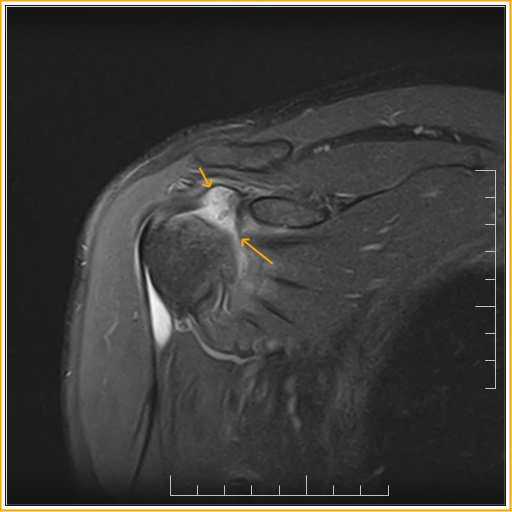

Capsulitis Rotator Interval . essential lesion involves the coracohumeral ligament and rotator interval capsule. the rotator interval capsule is the anterosuperior aspect of the glenohumeral joint capsule, which merges with the chl and sghl insertions medial and lateral to the. the mri changes of adhesive capsulitis are most often observed at the rotator interval and the inferior glenohumeral ligament. The coronal and axial views can also be helpful. contracture or scarring of rotator interval structures can manifest as adhesive capsulitis. adhesive capsulitis, also known as frozen shoulder, is an inflammatory condition characterized by shoulder stiffness, pain, and.

Adhesive capsulitis in a 59yearold patient. (a) Oblique sagittal PDw Capsulitis Rotator Interval the rotator interval capsule is the anterosuperior aspect of the glenohumeral joint capsule, which merges with the chl and sghl insertions medial and lateral to the. essential lesion involves the coracohumeral ligament and rotator interval capsule. contracture or scarring of rotator interval structures can manifest as adhesive capsulitis. the mri changes of adhesive capsulitis are most. Capsulitis Rotator Interval.